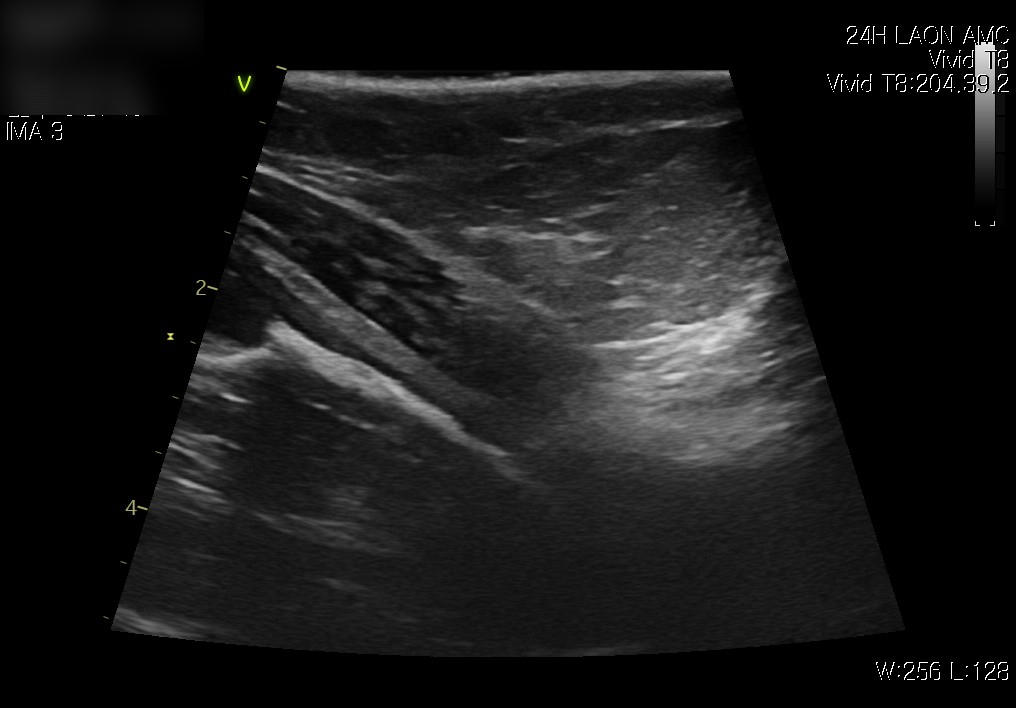

치료 후 방광 요도(좌) / 치료 후 방광 초음파 사진 / 출처: 라온동물메디컬센터

추적 초음파 검사에서도 방광 내 염증으로 인한 찌꺼기도 사라졌으며,  소변이 정상적으로 배출되는 모습이 확인되었습니다.  보호자님께는 방광염 재발을 예방하기 위해 방광염 처방사료의 식이 교체와 함께, 방광 보조제 급여를 권장드렸습니다.